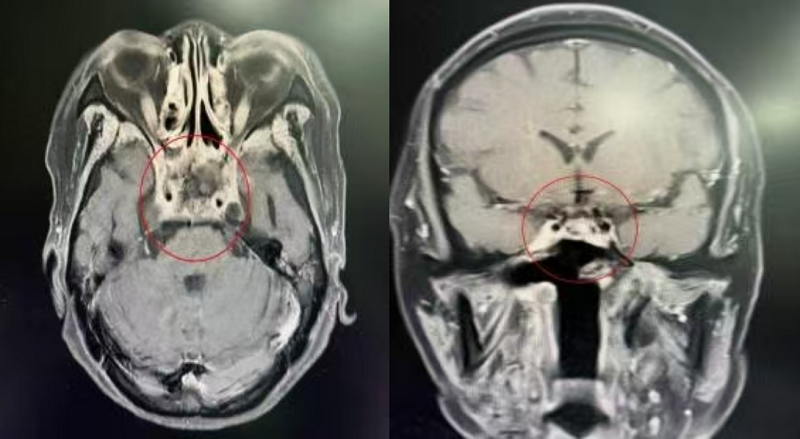

两例患者均为鼻咽癌复发经过再次放疗或化疗及靶免综合治疗后患者,病情已到极其凶险的地步:一例患者反复鼻出血,检查发现鼻咽部组织广泛坏死,颈内动脉被病变包绕,随时可能因致命性大出血而危及生命;另一例患者长期剧烈头痛,经反复抗炎治疗无法改善,辗转多家医院后发现颅底骨质及筋膜已大范围坏死,病变紧贴双侧颈动脉,破裂风险极高。

手术中,团队以“绣花”般的精细操作,在鼻内镜的辅助下,沿着病变边界小心翼翼地清除坏死组织,在毫米级的空间内精准保护颈内动脉、视神经等关键结构,成功为患者“拆除”了潜伏在颅内的“定时炸弹”。更具突破性的是,团队摒弃了传统人工材料修复方式,采用自体带血管蒂颞肌瓣转移修复技术,通过“取己之材,补己之缺”的方式,将患者自身血运丰富的颞肌组织精准转移并覆盖在颅底巨大缺损处,重建起一道密闭、坚固的生理屏障。这一技术不仅完美解决了颅底重建难题,更凭借自体组织高存活率、强抗感染的优势,从根本上杜绝了脑脊液漏、感染致颈内动脉大出血等致命并发症,为患者的安全康复筑牢了双重防线。

得益于术前周密的规划、术中的精准操作以及术后的精心护理,两例手术均取得圆满成功。患者术后恢复远超预期,住院期间未出现脑脊液鼻漏、颈内动脉大出血及严重感染等并发症,头痛、鼻出血等症状也迅速缓解,颞肌瓣存活良好,患者顺利康复出院。